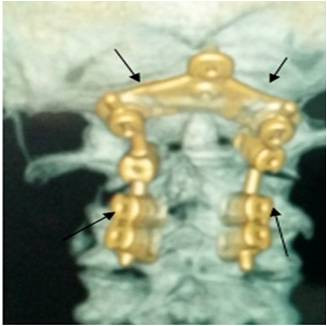

Պարանոցային հետին ֆիքսացիան կատարվում է վնասվածքների, ուռուցքների դեպքում կամ էլ կապանահոդային հյուսվածքի գերաճի հետևանքով առաջացած ողնուղեղի կոմպրեսիայի և միելոպաթիայի կապակցությամբ կատարված լամինէկտոմիայից հետո: Ահա այպիսի տեսք ունի կռանիոցերվիկալ ֆիքսացիան, որը համարվում է պարանոցային հետին ֆիքսացիայի տեսակներից մեկը: